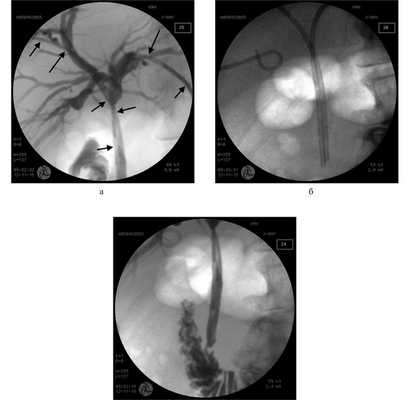

В принципе любое наружновнутреннее дренирование желчного дерева можно выполнять в супрапапиллярном варианте, но следует учитывать целый ряд лимитирующих обстоятельств, а именно адекватную проходимость большого сосочка двенадцатиперстной кишки, диаметр общего желчного протока дистальнее зоны окклюзии, который должен быть достаточным для уверенного расположения рабочего конца дренажа, избыточную подвижность наружновнутреннего дренажа и т. д. (рис. 3). В связи с этим типичным вариантом наружновнутреннего дренирования желчного дерева остается транспапиллярное проведение дренажа.

Рис. 3. Антеградные холангиограммы (а, в) и нативная рентгенограмма (б) пациента с опухолью Клацкина тип II по Bismuth. а - двустороннее супрапапиллярное наружновнутреннее дренирование (дренажи маркированы стрелками); б - в просвете общего желчного протока супрапапиллярно два мультиперфорированных дренажа 10Fr; в - в просвете общего желчного протока супрапапиллярно два мультиперфорированных дренажа 10Fr.